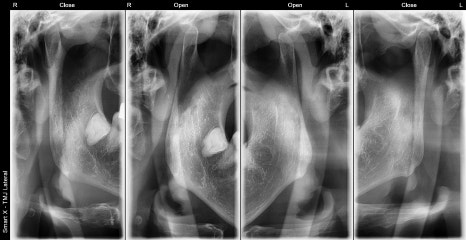

50대 남성 턱관절 환자의 초진 엑스레이 사진입니다.

파노라마와 관절 전용 촬영을 통해 양측 턱관절 디스크의 위치 이상(비대칭)과 관절 공간 협소 소견이 확인되었습니다.

✅ 턱관절 디스크까지 확인 가능한 파노라마

단순한 치아용 파노라마를 넘어,

서울오브치과병원에서는 턱관절 디스크와 관절 공간까지 확인 가능한 고성능 장비를 보유하고 있습니다.

턱관절 진단에 꼭 필요한 세부 정보를 이미지로 확인해

보다 정밀하고 예측력 있는 치료 설계가 가능합니다.